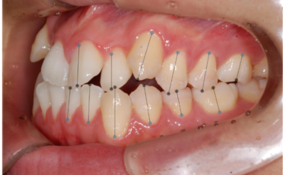

이미지/라벨링 예시

| 이미지 | 라벨링 | |

| left |

치아경계/치축/대구치관계

| right |

| front |

치아경계/치축